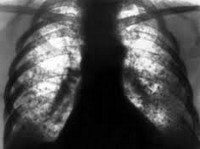

Рентгенография легких при силикотуберкулезе может отражать различную картину: на фоне диффузного крупно-сетчатого фиброза и типичных для силикоза симметричных узелковых высыпаний в средних и нижних долях появляются туберкулезные очаги, инфильтраты, силикотуберкуломы, каверны, преимущественно расположенные в верхушечных областях. Достоверность диагноза подтверждается при обнаружении МБТ в мокроте или промывных водах бронхов. Бронхоскопия помогает визуально определить пылевую пигментацию и признаки туберкулезного поражения слизистой бронхов.